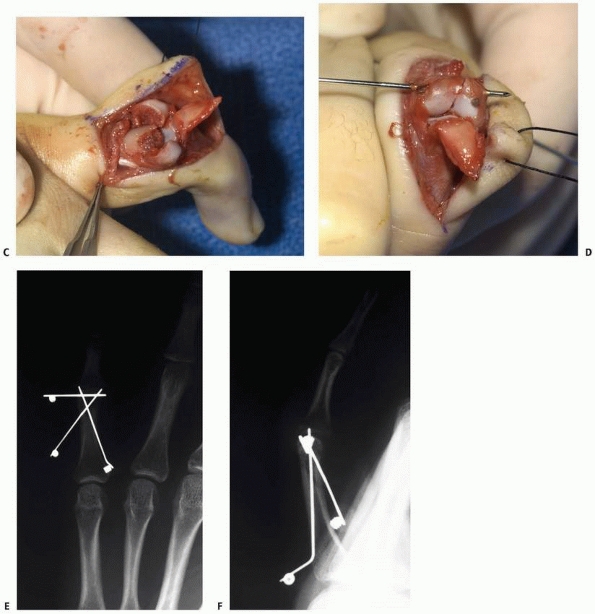

![]() |

FIGURE 8-32 A. A 10-year-old girl with a displaced unicondylar fracture of the ring finger proximal phalanx. B. Clinical examination reveals malrotation of the digit. C. Dorsal exposure with incision between lateral band and central slip. D. Exposure of displaced fracture fragment. (continues)

|

FIGURE 8-32 (continued) E. Fracture reduced with Kirschner-wire fixation. F.

Postoperative radiograph shows restoration of articular surface. (Courtesy of Shriners Hospitals for Children, Philadelphia, PA.) |